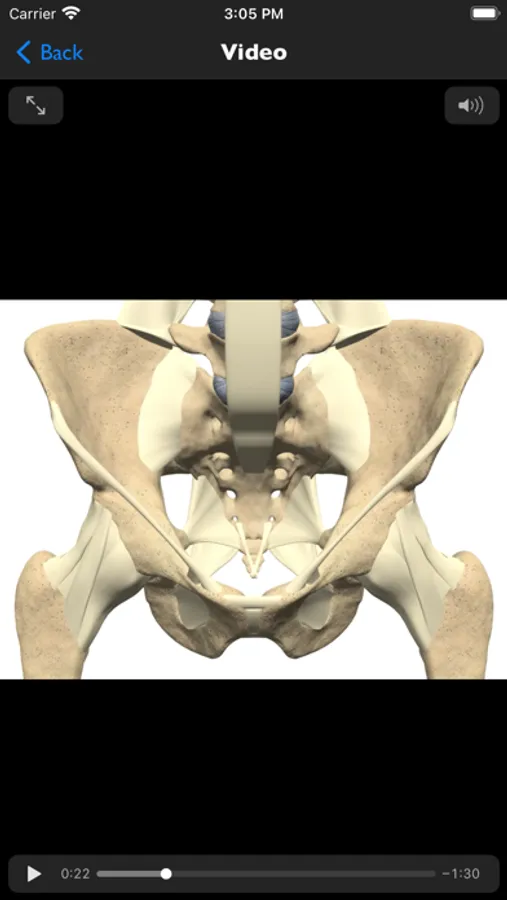

• 3D animations on the normal anatomy of the cervical and lumbar spine and the sacro-iliac joint

• 3D animations showing the progression of sacro-iliitis to fusion and syndesmophytes to ankylosis